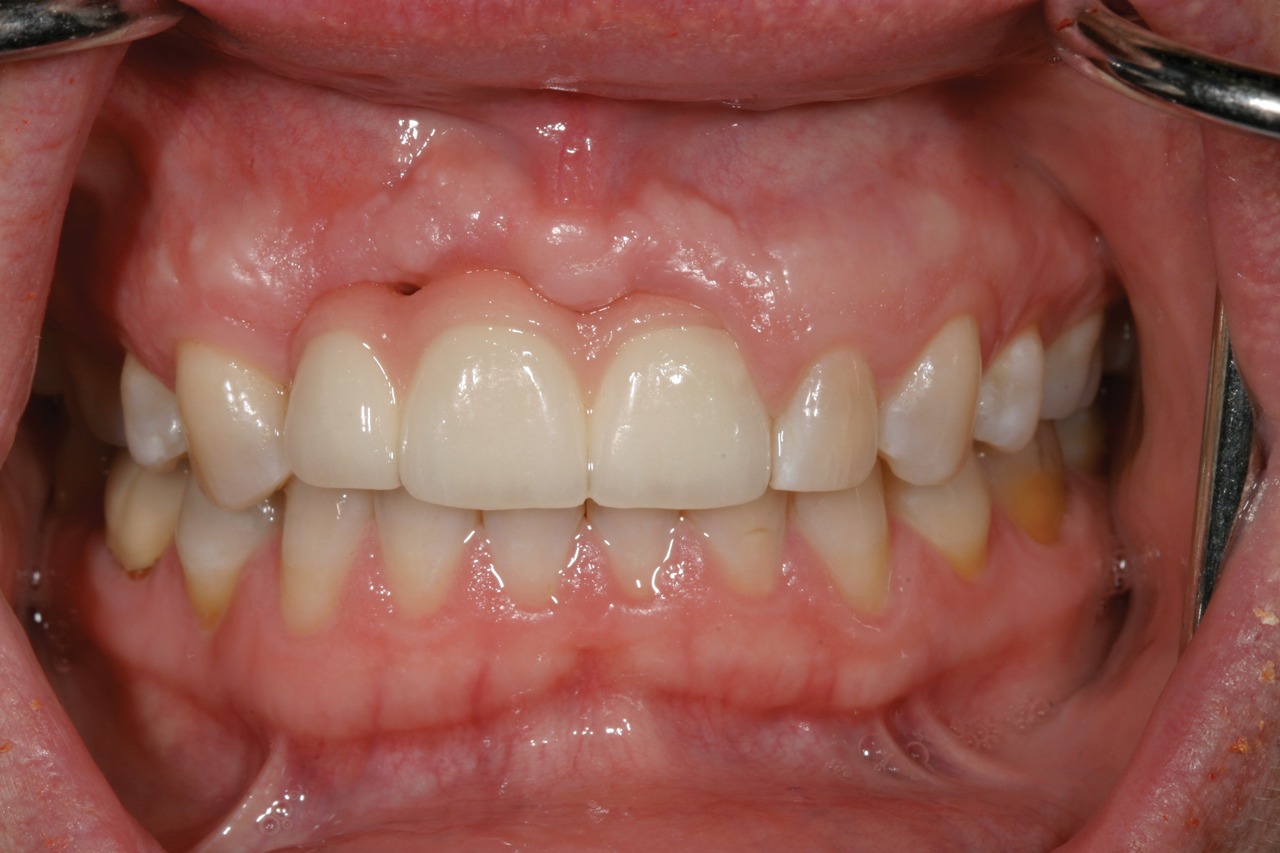

Fig 5. Successful final clinical result of the implant restoration and adjacent teeth.

Figure 5

Fig 11. Restoration at 24-year follow-up.

Figure 11